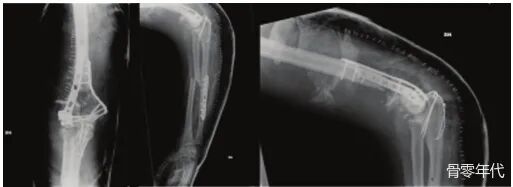

影像学表现